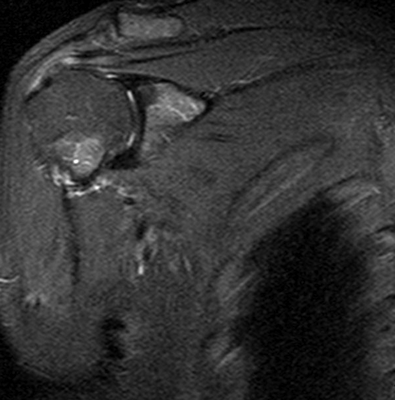

МРТ плечевого сустава, что показывает?

МРТ плечевого сустава

МРТ плеча

Расшифровка фото снимков МРТ плечевого сустава